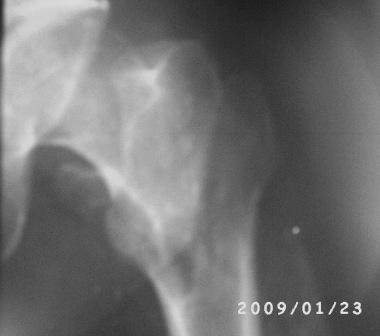

Двойной перелом бедра

Больному 50л. В отдаленном от центра р-не ДТП 6.12.08г. д-з " тяжелая ЧМТ, мн.перломы ребер слева,отрыв ножки селезенки, повреждение п/ж железы, з/двойной перелом прав.бедра.

После экстрен. хирургических вмешательств, конечность фиксирована кокситной гипсовой лонгетной повязкой. Кома 2 нед, нагноение п/о раны живота, посттравмат. пневмония. 20.01.09г. переведен к нам. Постельный больной, ослабленный,бледный, весом 56кг: свищ п/о раны перед. брюшной стенки с сукровичным выделением, гипс снят - деформация и укорочение бедра на 6 см, в обл перелома есть спайка. слабо, но активно поднимает ногу, контрактура т/б и коленных суставов. Обшеукреп. лечение, компоненты крови, общ. массаж, ЛФК и больной активизирован, начал ходить с костылями, движения в суставах почти восстановлены. НВ-112, эр-3,5млн. Наш план блокир. и/м остеосинтез. Имеется гвозди для ВНПБ ЦИТО, но PFN не имеется

. -Можно ли остеосинтез гвоздем для высоких и низких переломов бедра?